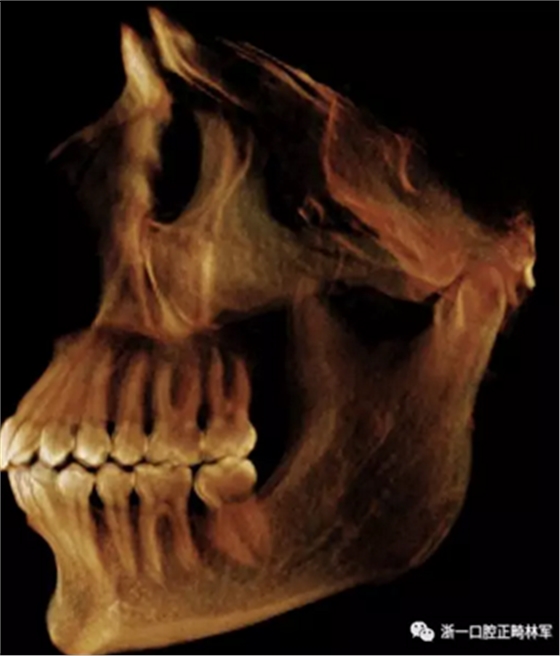

在輸出的3D模型上,使用體內(nèi)軟件(Anatomage,San Jose,Calif)將下頜骨以最小的間隔從顱骨上分離(圖5)用于保留下頜骨的咬合細節(jié),游離的下頜骨被保存(圖6,A)。同時,將沒有下頜骨的顱骨導出并保存(圖6,B)。

圖6. A,從整個3D模型上修剪的下頜骨; B,修剪的顱骨。

使用體內(nèi)軟件,第一次融合包括咬合導板在下頜牙齒上定位(圖7)。 圖8顯示了咬合導板和下頜骨(類似咬合導板/游離下頜骨)的完整定位。第二次融合涉及咬合導板的上頜牙齒與顱骨上的的上頜牙齒的定位(圖9)。除了原始的下頜骨最小牙尖分離的3D模型(圖10)之外,這將產(chǎn)生一個構(gòu)建好的下頜骨完全咬合的3D模型。